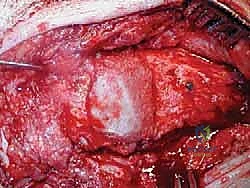

الخطوة الرابعة: تنظيف العظم والترقيع (Debridement and Bone Grafting)

يتم تنظيف الأنسجة الملتهبة والأكياس العظمية. ونظراً لأن مفصل (Agility) يترك فراغاً كبيراً بعد إزالته، يتم استخدام طعوم عظمية (Autograft من حوض المريض أو Allograft من بنك العظام) لملء الفراغات وبناء أساس قوي.

الخطوة الخامسة: تركيب المفصل الجديد أو الدمج

يتم إدخال المفصل الجديد المخصص للمراجعة، والذي يحتوي غالباً على سيقان (Stems) تدخل عميقاً في عظمة الساق وعظمة الكاحل لضمان الثبات الميكانيكي. في حال وجود كسور في الكعب، يتم تثبيتها في هذه المرحلة.